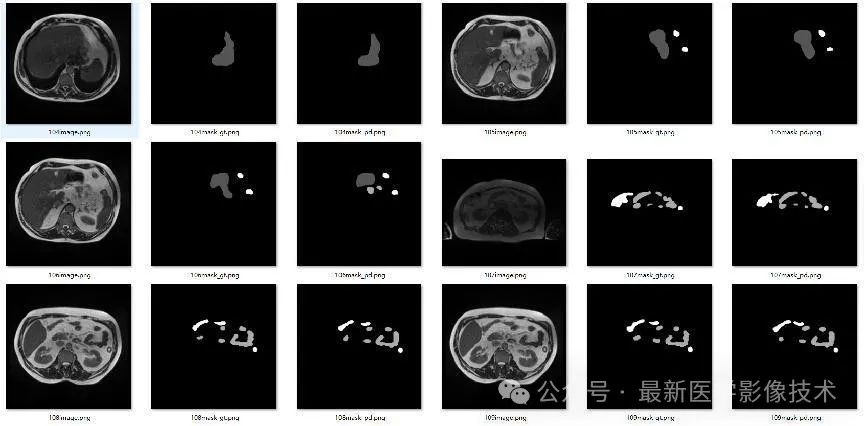

4、验证集部分分割结果